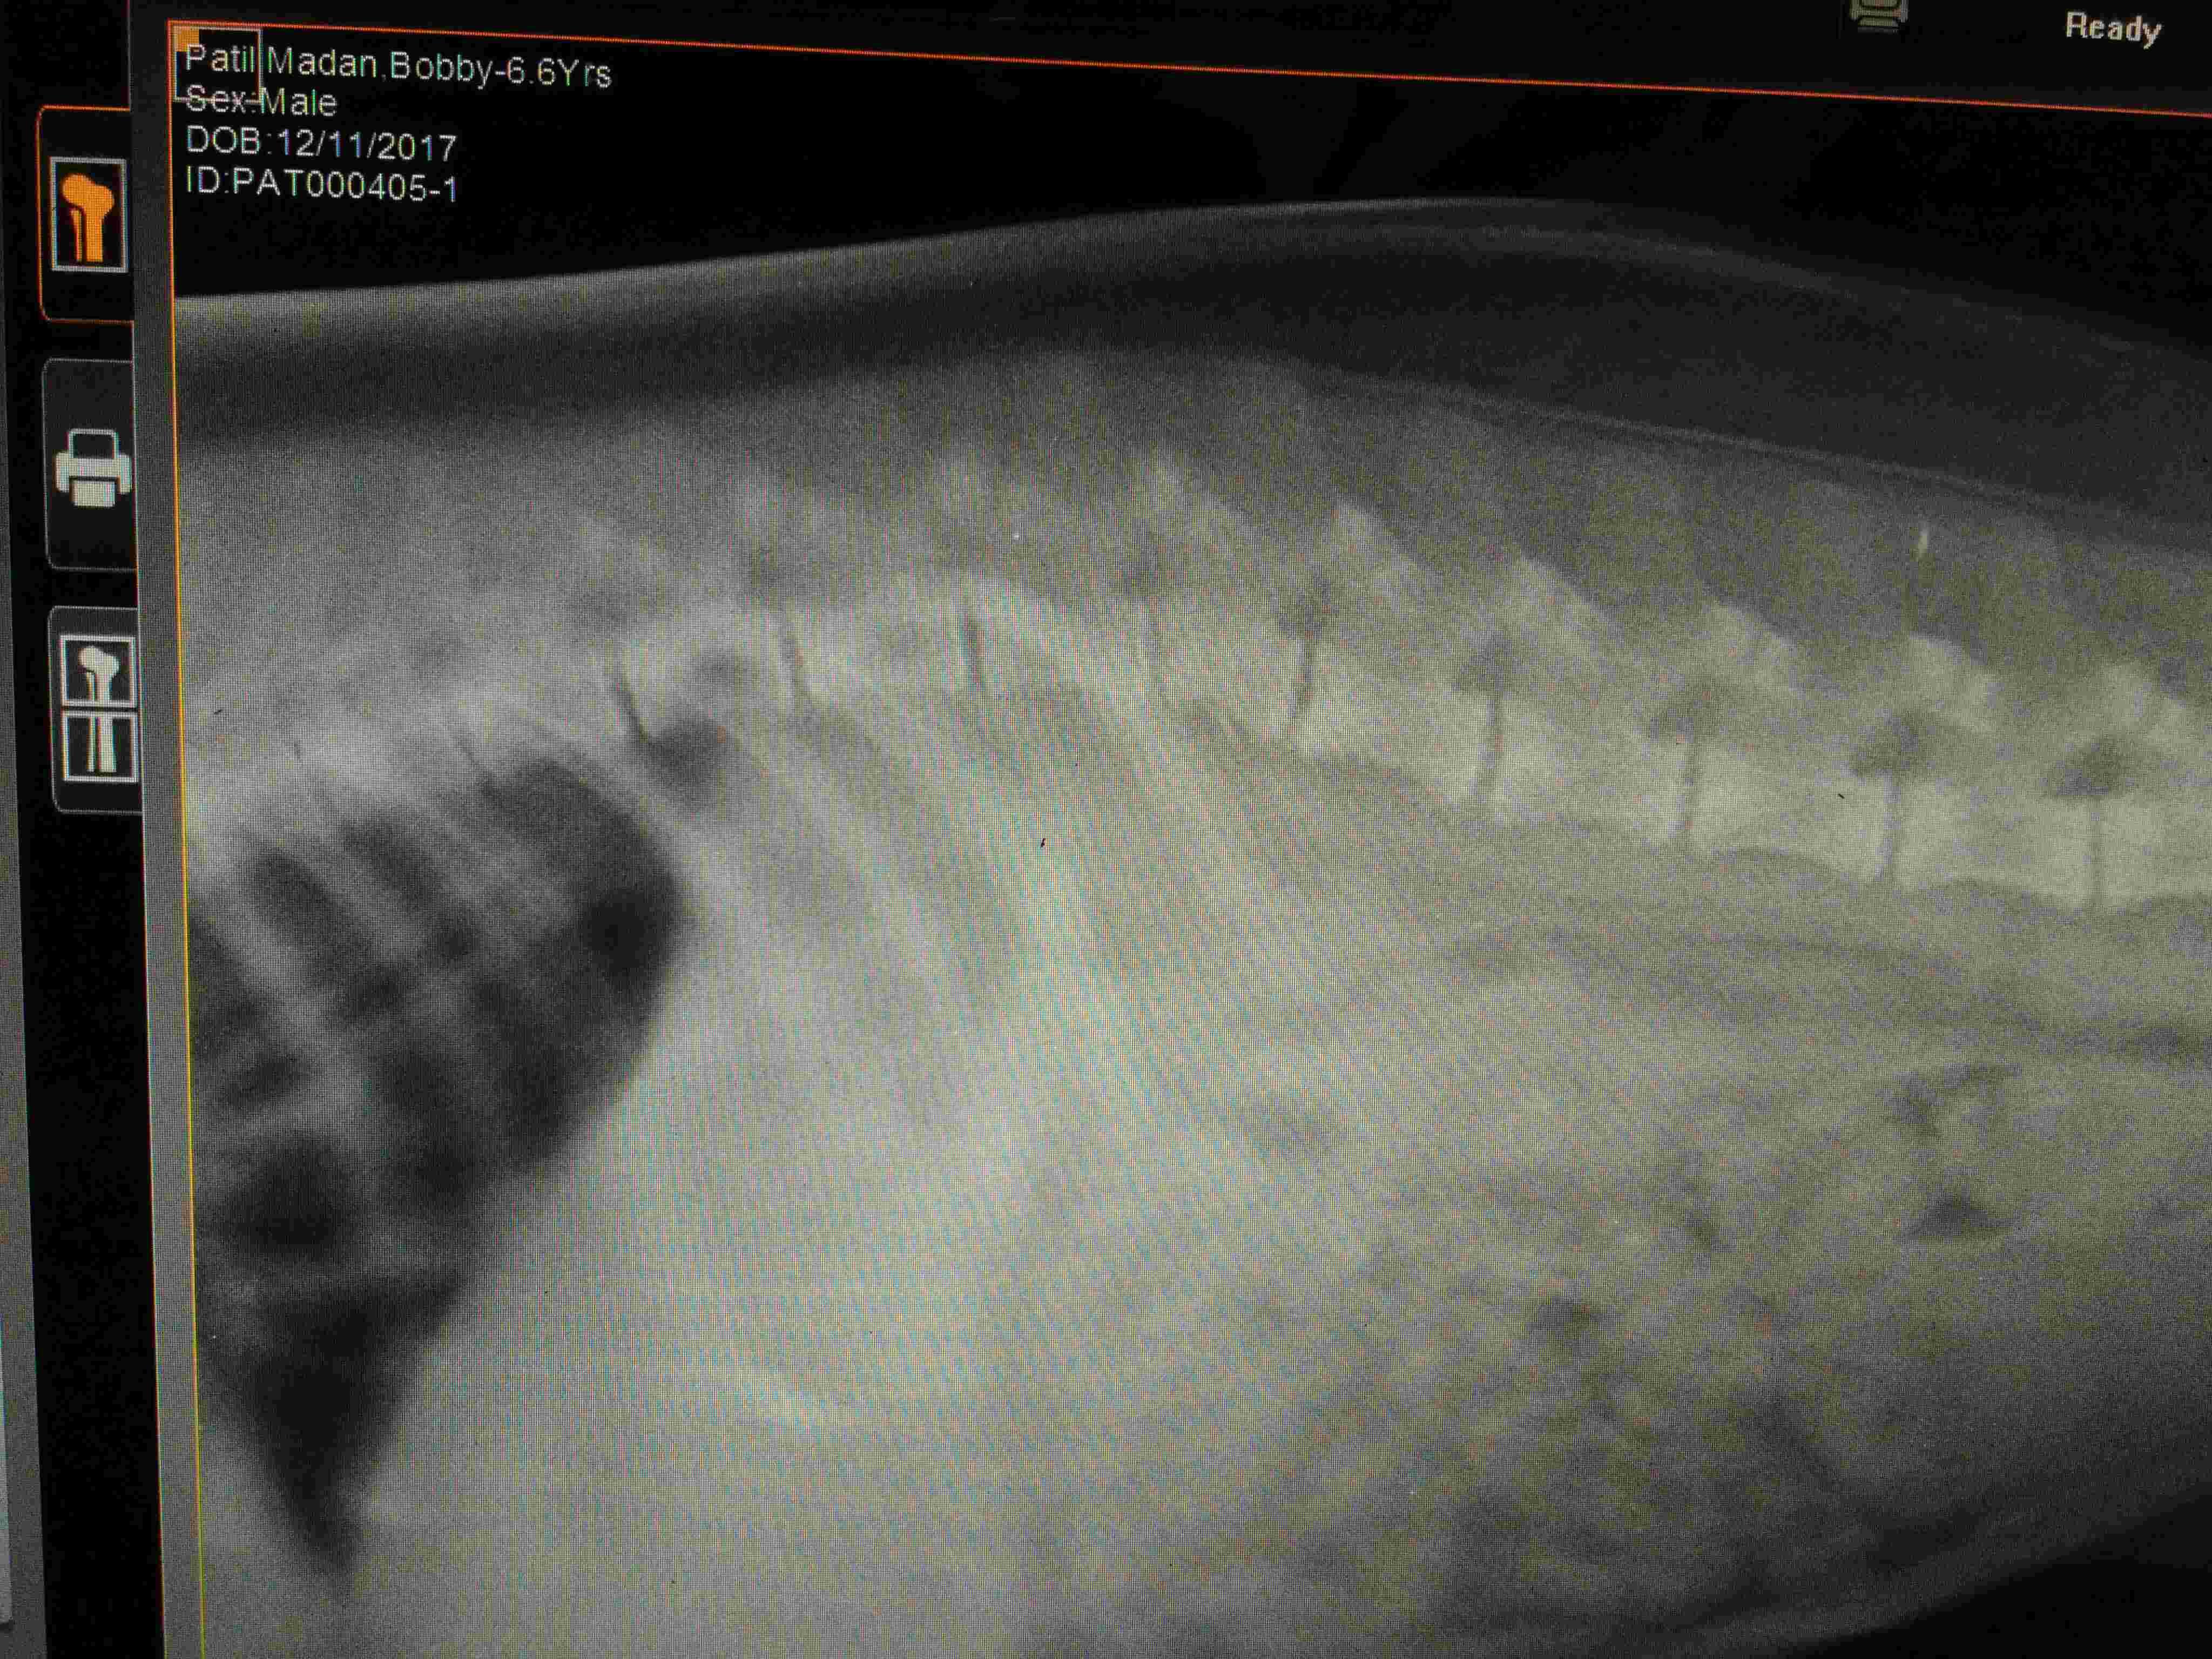

Dog fallen 20 feet on back bone he lost sense back two legs there is no fracture in bone but doc said no chance recover because spinal nurvous system damage i uoload xray pic tell me what to do with it how to recover i cant not get what to do hiw to recover him from this

I am so sorry that this has happened to Tommy. Unfortunately I cannot not say for sure if there is any chance of recovery from just X-rays. An MRI or CT really needs to be done to get the best view of the spinal cord and his intervertebral disks. Also, you may want to see if there is a veterinary surgeon who is comfortable with back surgery as this could be an option for Tommy. If not, the only other suggestion would be high doses of steroids. None of these options are guaranteed to work but they might. I hope this helps and hope that Tommy is capable of healing. Hang in there and good luck.